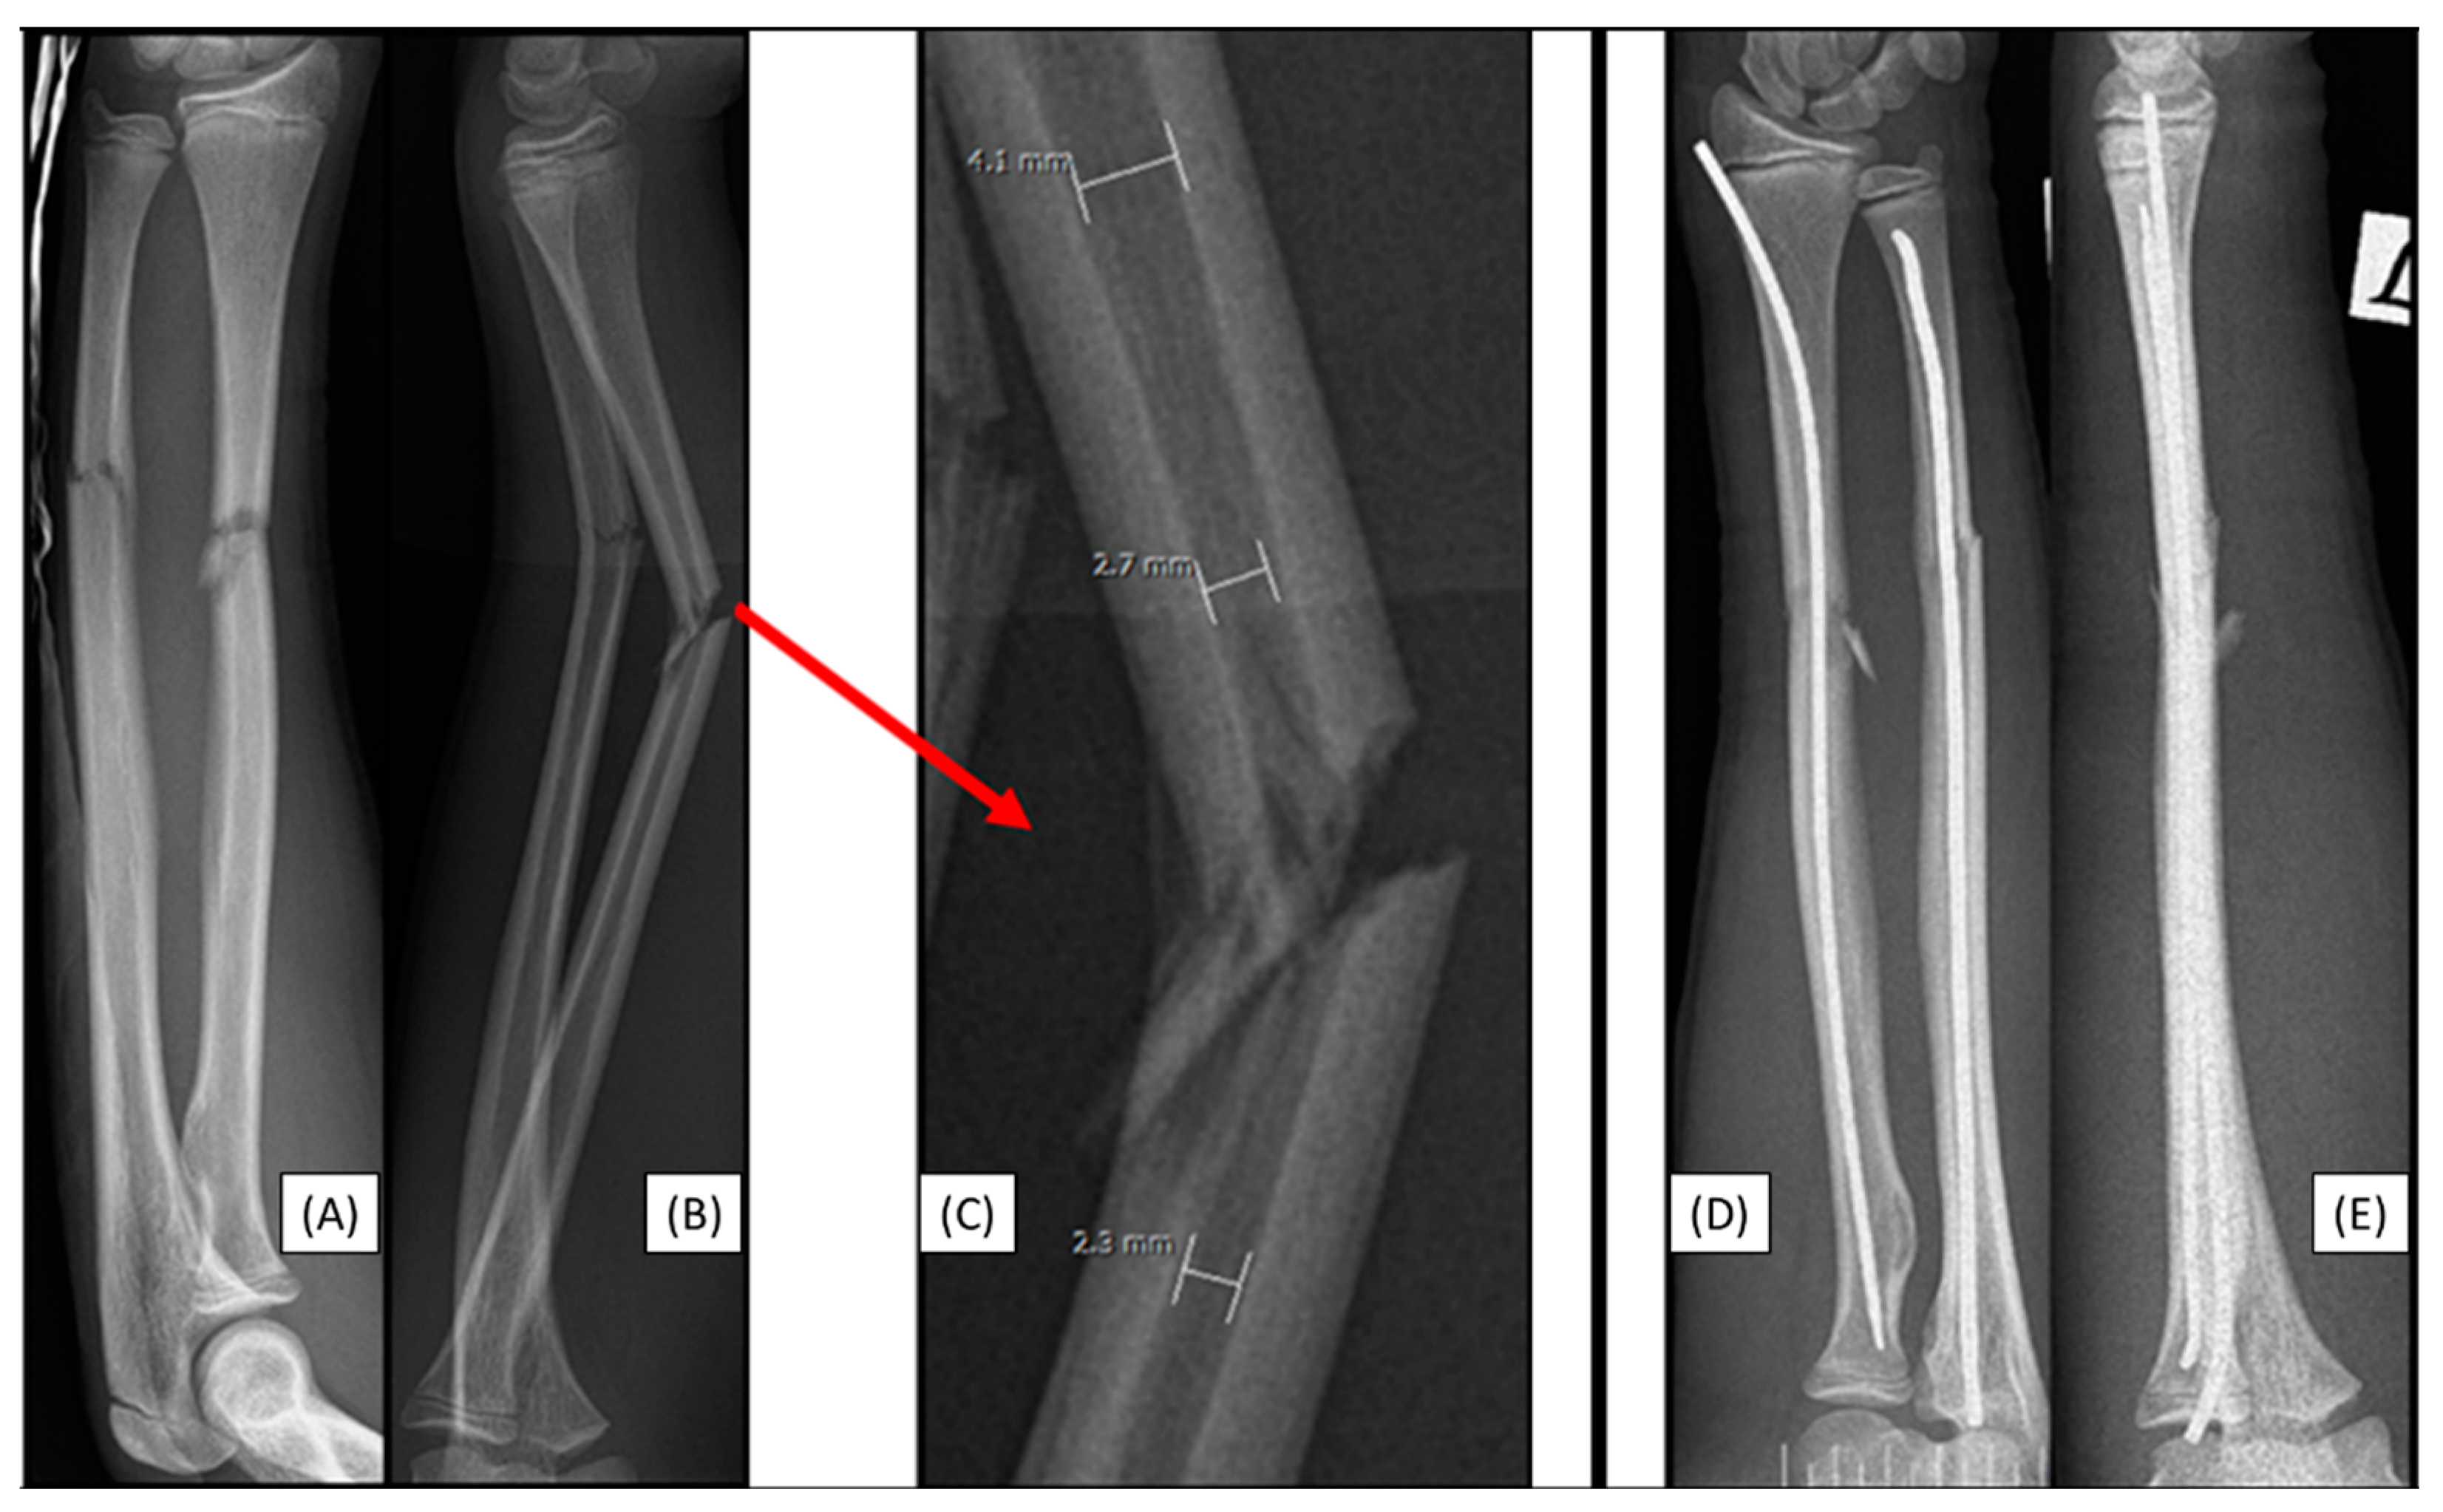

3.1. Case 1: Iatrogenic Cortex Perforation

A 12-year-old boy's left forearm was injured during a handball match. X-rays confirmed a distal dia-metaphyseal forearm fracture. Following the closed reduction of a left distal diaphyseal forearm fracture, due to instability, the (2.7 mm) dilator was introduced through a typical radial approach, which resulted in cortical perforation on the opposite side (Figure 1(C)). Preparation of the medullary cavity is crucial when using absorbable IM implants. Although this patient case did not involve an implant-related complication, it directly relates to the challenges associated with the surgical procedure. Therefore, when such intraoperative complications are observed, the use of absorbable implants is not recommended.

Figure 1. Primary X-rays of a distal diaphyseal forearm fracture from anteroposterior (AP) and lateral views (B). After the insertion of the dilator (blue line), the opposite cortical was perforated (red line). Following this intraoperative complication, elastic nails were inserted, and both bones were stabilized with ESINs. Postoperative X-ray demonstrates good alignment (C).